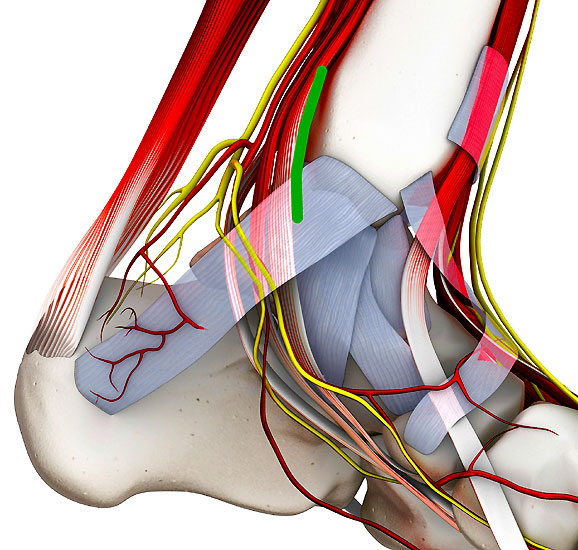

Abbildung 2: K-Draht Spreizer. Dieser erlaubt eine Distraktion des Gelenks über 1,8 mm Kirschnerdrähte. Diese Technik hilft in nahezu allen Fällen eine Innenknöchelosteotomie zu vermeiden.

Abbildung 2

• Spreizer mit Bohrungen für Kirschnerdrähte (Abbildung 2).